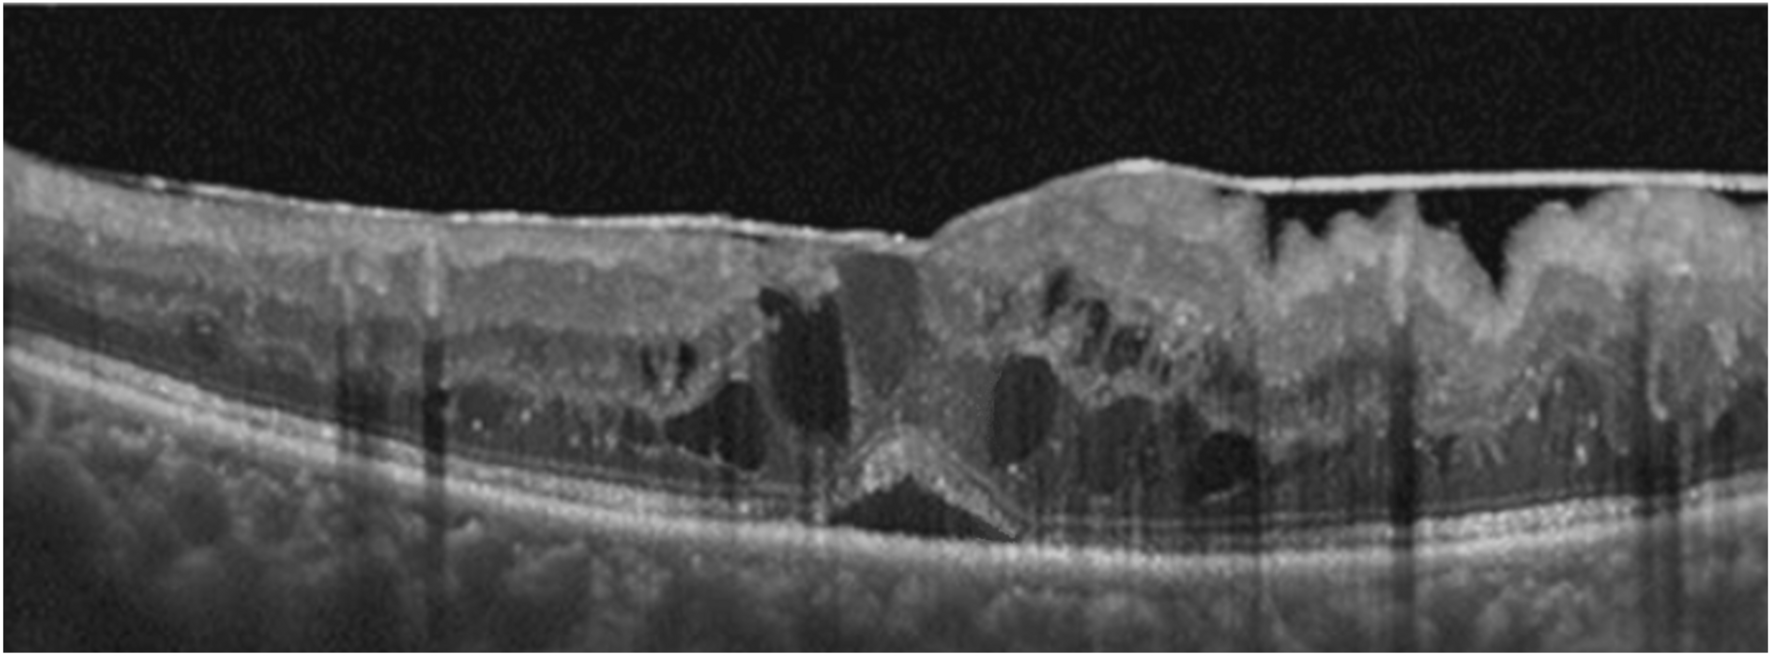

Figure 1

Optical coherence tomography scan showing tractional diabetic macular edema (tDME) with cystoid and retinal detachment pattern, and epiretinal membrane. A representative case.